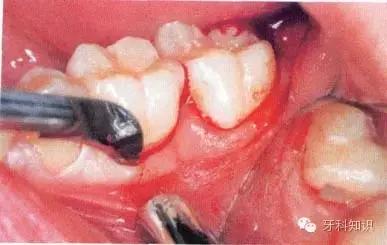

a第Ⅱ类,b分类中位阻生。左下颌第三磨牙阻生,位于黏膜下。磨牙后区切开后,作近中切口,使用12号刀片沿牙龈扇贝状外形切透龈沟至牙槽嵴顶,避免将龈乳头切除。图中近中切口延长至第二前磨牙,便于翻瓣,更好地显露磨牙后区的骨质

b翻瓣后,阻生牙的(牙合)面位于第二磨牙颈部及其牙槽嵴顶均清晰可见。切割牙体前先去除舌侧骨板以保护软组织